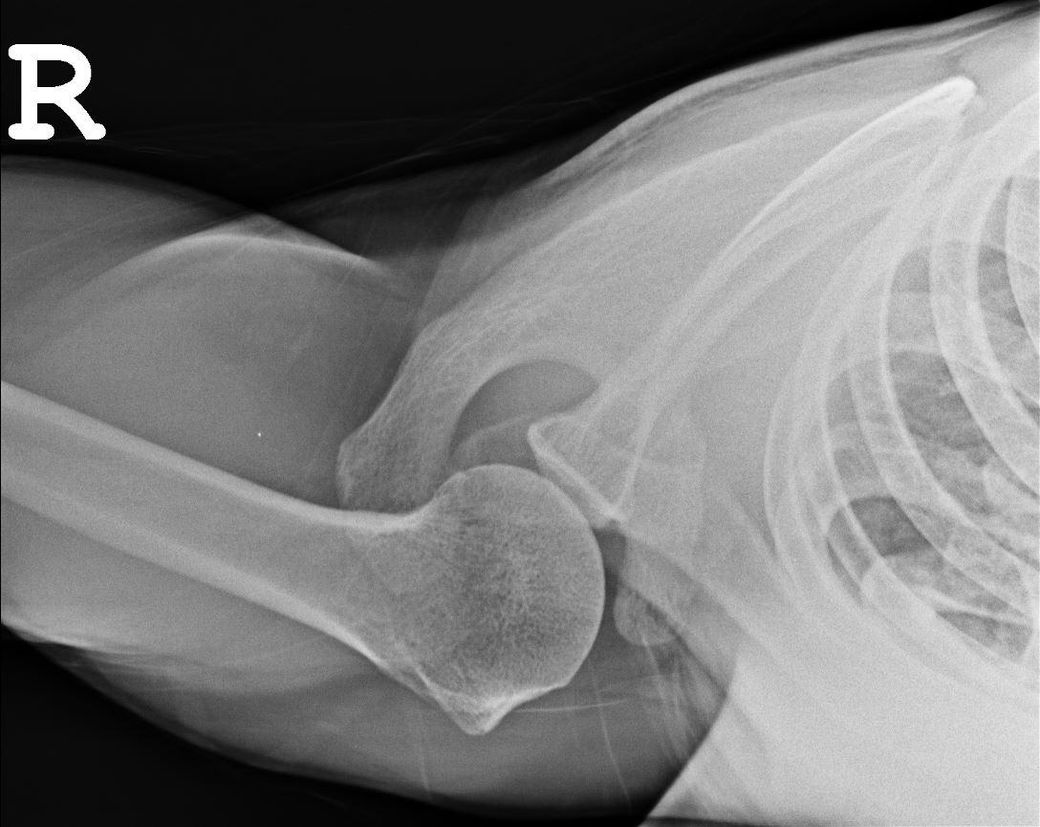

엑스레이 사진상 어깨탈구 소견이 있나요?

하기 사진은 그날 찍은 어깨 엑스레이입니다.

혹시 엑스레이상 어깨 탈골 소견이 있는지 궁금합니다.

업로드 하신 어깨 엑스레이 사진에는 딱히 보이는 이상소견이 따로 있지 않습니다. 어깨 부위 탈구 소견이 관찰되지 않으며 정상 어깨 엑스레이 사진으로 보입니다. 어깨의 탈구가 있으면 심한 통증과 함께 움직임에 제한이 생기므로 단순히 소리가 나는 소견만으로는 탈구에 대해서 크게 걱정을 할 필요는 없습니다.

올려주신 어깨 엑스레이를 보면 뼈구조가 정상적으로 위치하고 있으며 명백한 탈구나 골절 소견은 보이지 않습니다. 어깨 관절은 비교적 안정적인 상태로 보입니다. 다만 어깨에서 뚝소리가 나는 것은 관절이나 힘줄, 인대가 움직이면서 나는 소리일 수 있으며 반드시 탈골을 의미하지는 않습니다! 통증이 없고 움직임도 정상적이라면 큰 문제 가능성은 낮습니다!안녕하세요. 김현태 물리치료사입니다.